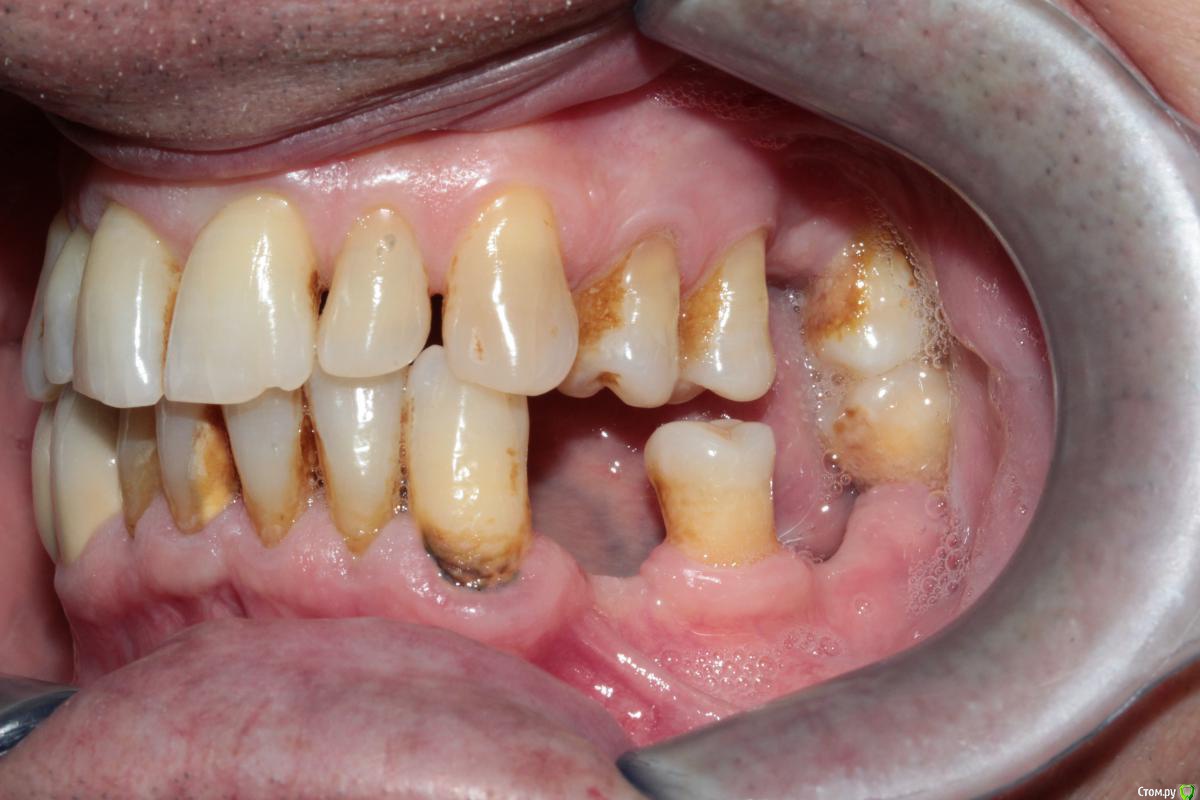

37ой зуб я уже удалил, сначала сделал ревизию, обнаружен был кариес корня по фуркации, поэтому удалили. На данный момент пациент не может полноценно жевать.

Меня больше смущает 2 момента, 1й - это то что на верхней челюсти зубы "разбросаны" как попало, не знаю что можно сделать не собрав их вместе предварительно. 2ой - в 4ом сегменте мост, консольный, его снимать не хочется, так как его по сути недавно поставили, а не сняв его не знаю что можно сделать в 3ем сегменте, если имплантацию откидываем как вариант....

P.S. - не совсем понятно как получилось  так, что фронт в контакте а премоляры вне контакта (слева).

Если вариант с имплантацией не рассматриваем 100%,то либо бюгеля,либо мосты.В случае НЧ,консольный зуб в крайнем случае можно отпилить,чтоьы не снимать весь мост,сделать мост 33-35 и кламмерный бюгель.На ВЧ аналогично,либо мосты,если 16 рискнете под опору,либо кламмерный бюгель

спасибо за ответ. Я с вами полностью согласен, хороший план, но меня вот беспокоят два момента: 1й - на верхнюю челюсть если сделать бюгель с кламмерами, то в области 24,25 там маленький зазор, а между 25 и 27 там зазор такой, что зуб вроде бы не поместится, в таких случаях там зуб не ставить? просто каркас?

2й момент - слева премоляры вне контакта, если работать под существующий прикус (скорее всего так и будем работать) то они опять останутся без контакта, это не будет проблемой?